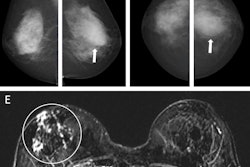

A total of 9,547 cases were included in the evaluation during the period from December 2023 to March 2024. The AI and the human readers agreed in 86.7% of cases. The recall rate for AI was 13.6%; the human double reader recall rate (which included consensus discussion) was 3.2%. This included consensus discussion; the authors add that their unit's average recall rate before consensus ranges between 5% and 5.5%.

Positive discordant and negative discordant rates were 11.9% and 1.5%, respectively. Of the 1,135 positive discordant cases (flagged by AI but not by the human readers) reviewed, one patient was recalled for an area of perceived parenchymal distortion. The patient was subsequently assessed with CT, ultrasound, and clinical evaluation, all of which were normal. The authors noted that she remained healthy at the time of writing their article.

Of the 139 negative discordant cases (i.e., those flagged by human readers but not by AI) reviewed, the AI missed eight cancers recalled by human readers. Of those eight, seven had been flagged by both readers and one by one reader. With a total of 91 cancers detected over the evaluation period, this constituted a missed cancer rate of 8.79%.

Furthermore, when these results were analyzed, there was no consistency in the types of cancers missed, nor did the type of breast tissue -- dense, fatty, or mixed -- show a pattern.